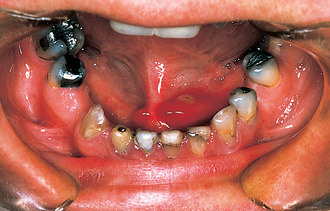

image

Fig. 14.5 A stone in the left submandibular duct can be seen ulcerating through the duct wall.

The typical presentation of a submandibular calculus is acute pain and swelling at meal times. Onset is rapid, within a minute of starting the meal, and the swelling resolves over a period of about 1 hour, after the meal is completed. However, this classical picture occurs only when the stone causes almost complete obstruction, often when it is impacted at the opening of the submandibular duct. More often the stone causes only partial obstruction and is lying either within the hilum of the gland or within the duct in the floor of the mouth. In this situation the patient may complain of occasional swelling, often with minimal discomfort, or of a chronically enlarged mass in the submandibular triangle with episodes of dull aching pain. This results from chronic bacterial infection, usually due to S. viridans, arising in an obstructed gland with salivary stasis and poor emptying. Often a salivary stone is totally asymptomatic and is discovered coincidentally during radiography for other reasons.